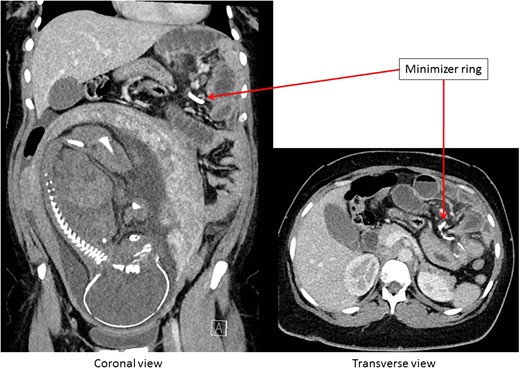

Computed tomography (CT) of the abdomen suggested dislocation of the minimizer ring possible internal intestinal herniation and dilation of the intestines (Fig. 1). No free air or fluid was identified. Contrast filled the gastric pouch and a small part of the alimentary limb. Further passage of contrast was not observed.

CT-scan of the abdomen showing an ileus caused by a migrated minimizer ring.